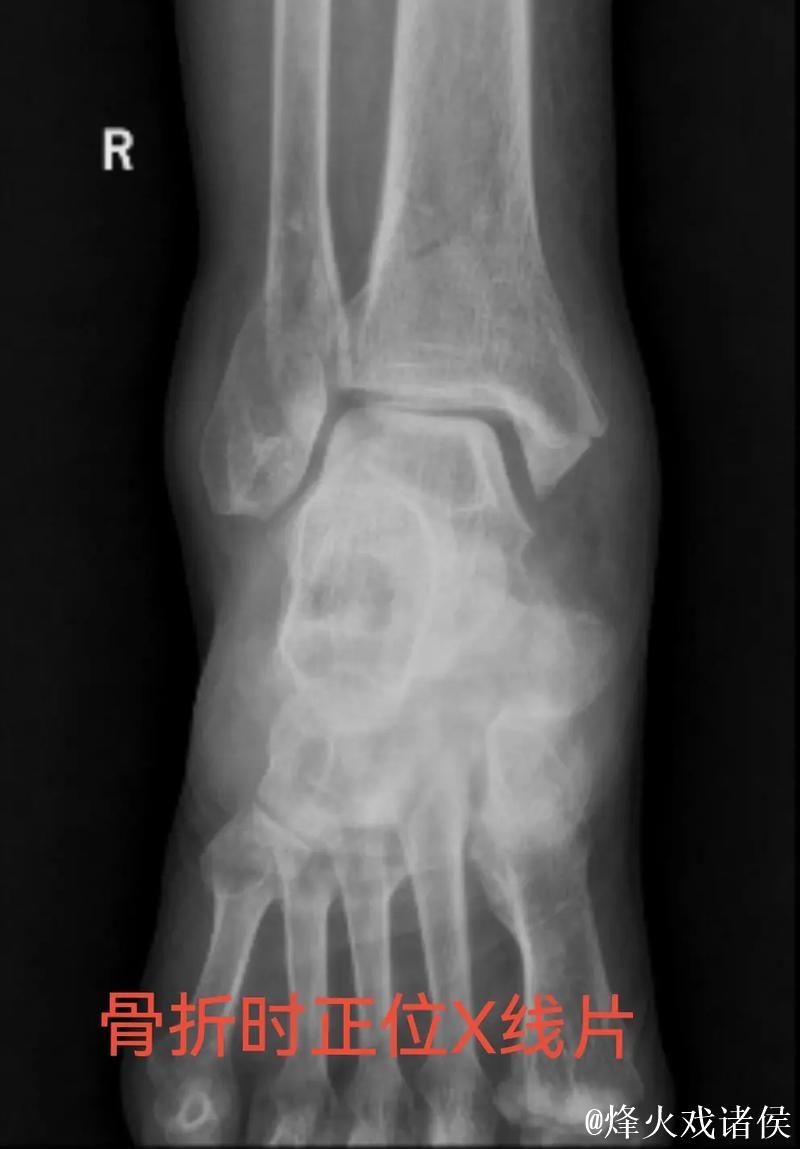

很多人在看到“右踝三角韧带断裂 右侧腓骨骨折”这样的医学表述时,只会感觉到“很严重”三个字,却未必真正理解其中的含义。踝关节三角韧带位于脚踝内侧,是一个由多条韧带组成的“组合体”,主要负责保持踝关节的内外稳定,防止小腿和足部出现异常翻转。当运动员在高速突破、急停、变向或落地时,如果脚踝遭遇过度外翻或扭转,三角韧带就可能被强行拉伸甚至撕裂。完全断裂不仅会造成剧烈疼痛,还会直接破坏踝关节的稳定性,使人几乎无法正常负重行走。与之同时出现的右侧腓骨骨折,大多与剧烈外力撞击或扭转应力有关。腓骨虽然不像胫骨那样承担大部分体重,但在踝关节的力学链条中起到重要支撑和协同作用。当韧带与骨骼在一次意外中同时受损,就意味着踝关节遭遇了极端应力,恢复与康复的难度成倍增加。

对于三角韧带断裂与腓骨骨折这种组合伤情,医学团队通常会综合评估踝关节稳定性、骨折位置与移位程度、软组织损伤范围,来决定是否采用手术治疗。若存在明显关节不稳或骨折移位,往往需要通过钢板、螺钉或钉棒内固定来重建骨性与韧带结构。在此之后,便是漫长而细致的康复周期。一般而言,骨折在数周内可以初步愈合,但韧带修复与功能恢复远比“骨头长好”更复杂。康复过程需要一套循序渐进的计划:早期的消肿与被动活动、中期的肌力与本体感觉训练、后期的专项运动模拟。每一个阶段若处理不当,都可能导致关节僵硬、力量不足或反复崴脚等后遗症。对职业运动员来说,问题不仅是“能不能走路”,而是“能不能继续高强度比赛、能不能保持原有水平”。任何轻微的落差,都可能在激烈竞争的职业舞台上被放大。